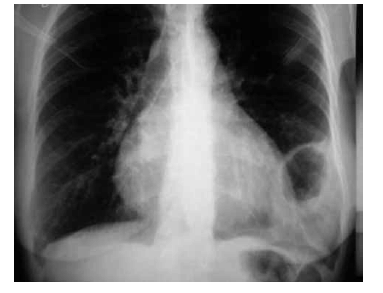

Uma paciente de 30 anos de idade deu entrada no prontosocorro de cirurgia com queixa de dor constritiva, contínua e de moderada intensidade em hipocôndrio esquerdo. A dor era sentida também no ombro esquerdo, incomodando-a. Havia dado a luz há 30 dias e foi orientada a usar cinta abdominal. História de acidente automobilístico há um ano. Ao exame, se encontrava com fáscies de dor e abdome sem alterações. Murmúrio vesicular diminuído em base esquerda. Foi solicitada radiografia de tórax, conforme ilustrado na figura acima.

Considerando o quadro clínico descrito acima, julgue os itens a seguir.

O sinal de Kehr presente sugere alteração diafragmática ou subdiafragmática.